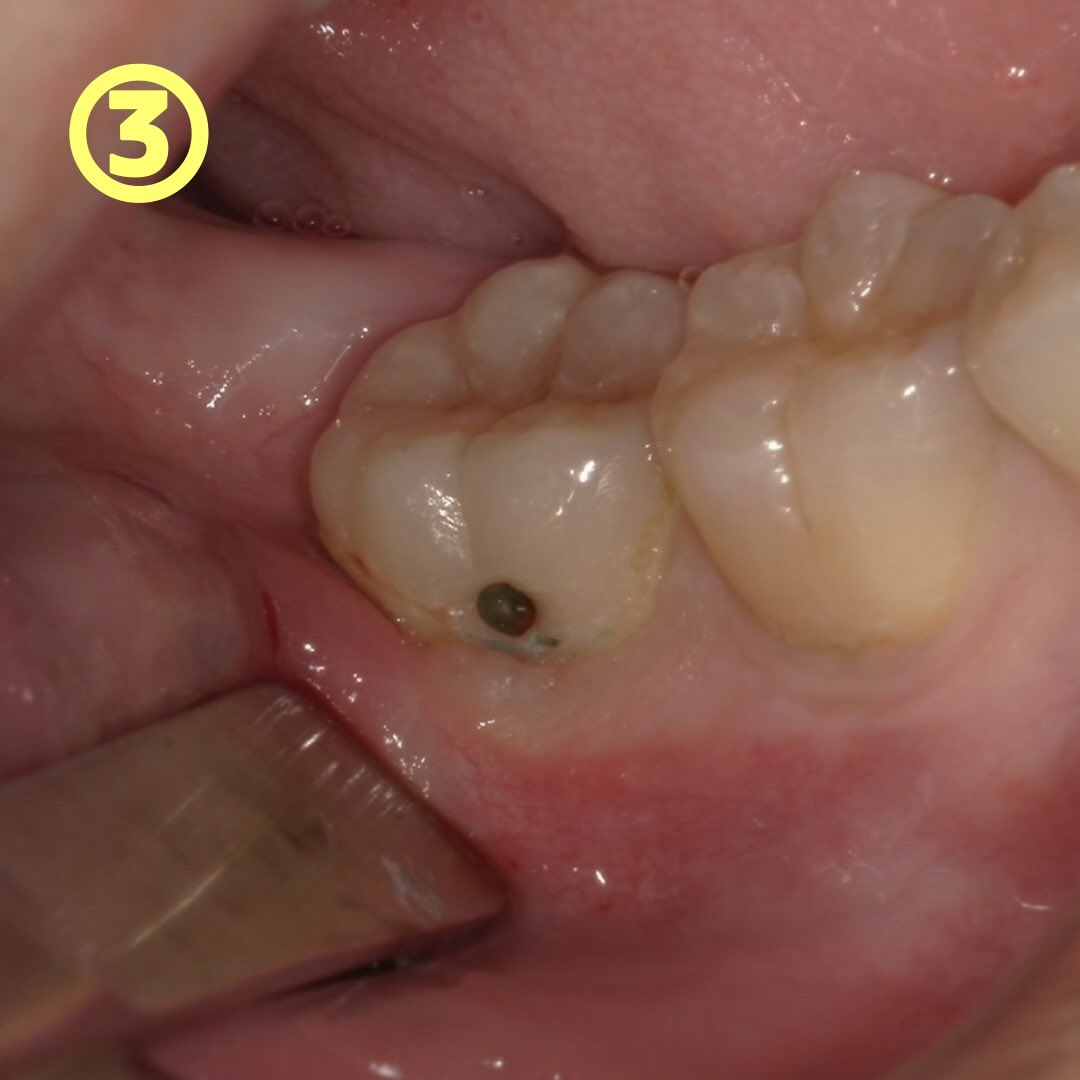

虫歯治療では、虫歯の取り残しがないように「う蝕検知液」という薬液を使いながら行うことがあります🙆♀️

一見虫歯が取り切れたようでも、隠れて残っている虫歯を発見するのに役立つのです👀

当院では青いう蝕検知液を使っています💊

②の写真の際に染め出してみました。→写真③